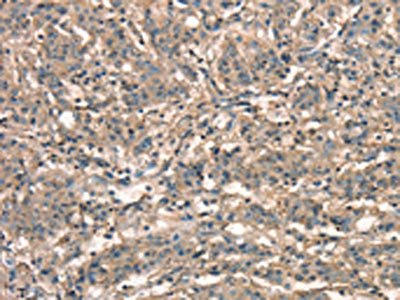

The image on the left is immunohistochemistry of paraffin-embedded Human brain tissue using CSB-PA010692(APC Antibody) at dilution 1/25, on the right is treated with synthetic peptide. (Original magnification: ×200)

The image on the left is immunohistochemistry of paraffin-embedded Human gastric cancer tissue using CSB-PA010692(APC Antibody) at dilution 1/25, on the right is treated with synthetic peptide. (Original magnification: ×200)